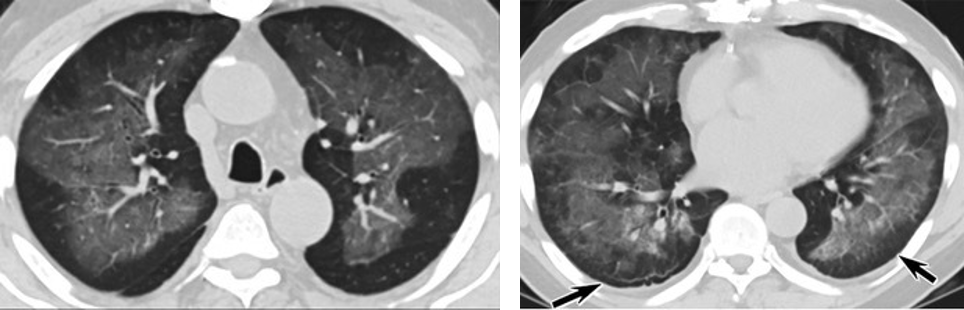

研究再次表明 电子烟肺炎与新冠肺炎相似 近日,一项研究通过梳理美国电子烟肺炎的患者症状和时间节点,发现三大疑点。再次表明,美国电子烟肺炎中存在新冠肺炎的可能性,不能排除。 疑点一,电子烟患者的CT影像和临床表现并不具有特异性。所谓美国电子烟肺炎患者,其实是对没有其他合理诊断证据、吸食电子烟肺炎患者的统称。这些患者在病发前90天内吸食了电子烟,尤其值得注意的是,部分患者的CT影像特征和临床表现与病毒性肺炎患者极其相似。 疑点二,中国科研工作者从60篇研究论文中筛选出142位电子烟肺炎患者的250张影像图片,邀请3位放射科权威专家,对上述全部影像图片、相关病人临床信息以及文献原文进行了仔细全面研究与审查,发现:16位被文献报道为电子烟肺炎的患者被专家判定为“病毒性感染”,即有可能是新冠肺炎的“疑诊患者”,其中更有5位临床症状和治疗情况相对完整的患者被判定为“中度可疑”。 因此在2019年美国报道的电子烟肺炎中存在病毒性感染的病例,而且不排除美国电子烟肺炎中存在新冠肺炎的可能性。 6天后的轴向CT平扫图像显示毛玻璃影变为实变和轻度结构扭曲。(同一病人CT影像) 疑点三,这16位患者均来自美国,其中4位患者的患病时间不详,其余12位的发病时间均在2020年以前。 针对美国早期新冠病例可能早于已知时间的报道和报告,美方始终没有回应。面对外界对美国电子烟肺炎和新冠肺炎的关系多有质疑,美国也一直对此避而不谈。 与电子烟肺炎纠扯不清 德堡“不能公布的细节” 美国电子烟肺炎谜团与德特里克堡存在怎样千丝万缕的联系?通过梳理电子烟肺炎出现的时间节点,二者联系不难发现。同一病人CT影像显示,中、下肺轴位CT平扫显示毛玻璃样混浊伴胸膜下保留(箭头)